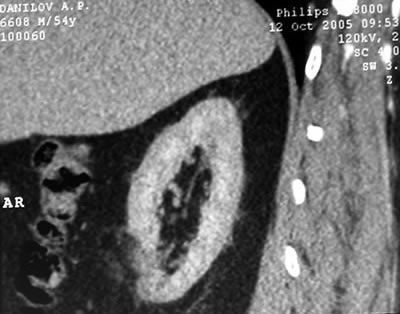

Спиральная

компьютерая томография (СКТ)

в нижнем сегменте правой почки

образование размером 30х33х36 мм, не накапливающее

контрастное вещество (max 15 HU).